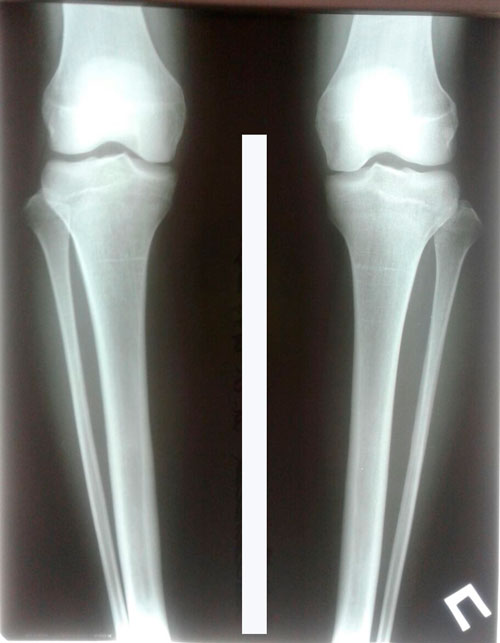

Пациентка- 20 лет. Павлодар.

Дата операции 17.01.2018г.

Ротация двойная.